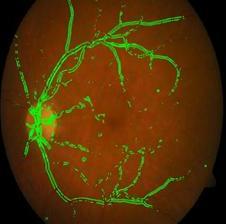

Fig. 9, 10 shows the detected blood vessels in normalandDRaffectedfundusimages.

Fig 10:DetectedBlood VesselsinaDRaffected RetinalFundusImage